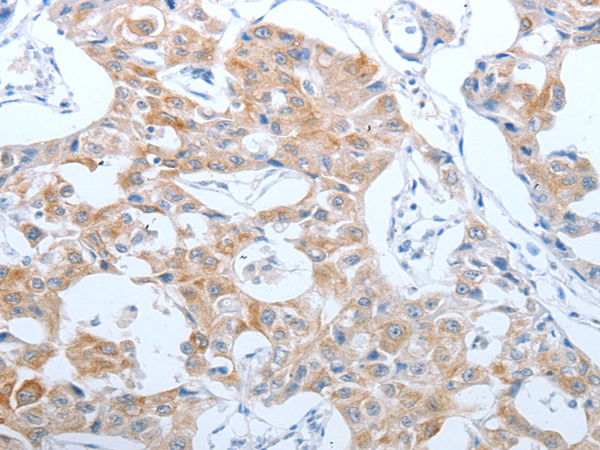

分类: 科研抗体货号: P10745别名: CEA cell adhesion molecule 5,CEA, CD66e应用: IHC反应种属: Human